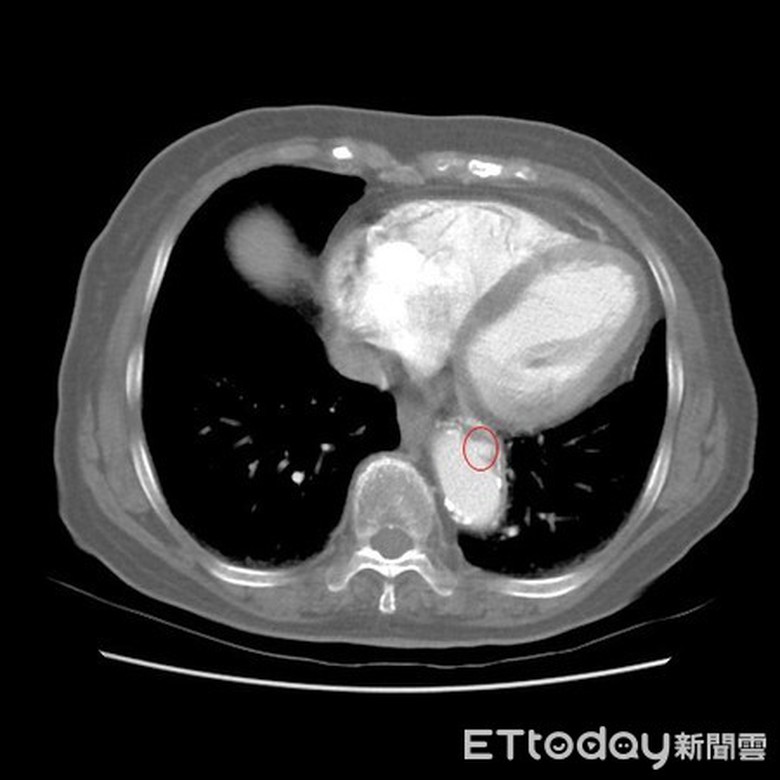

Bác sĩ cho biết, bà mắc bệnh phình động mạch chủ. Trong giai đoạn đầu, căn bệnh này không có triệu chứng, còn được mệnh danh là “kẻ giết người thầm lặng”. Khi bị đau tức ngực, đau lưng, khàn giọng, khó thở thì phải đi khám càng sớm càng tốt.

Liu Yinzuo, Trưởng khoa Tim mạch, Bệnh viện Đại học Ajou chỉ ra rằng, động mạch chủ là một mạch máu lớn có chức năng dẫn máu đến tim và phân phối máu đi khắp cơ thể. Trường hợp của bà Trần đã khá lớn tuổi nên thành động mạch đã bị vôi hóa, tính đàn hồi thành mạch kém, máu lưu thông kém hơn. Khi bị kích thích liên tục làm cho đường kính của động mạch chủ trở nên to bất thường và tạo thành túi.

Bác sỹ Liu Yinzuo nhắc nhở rằng, bệnh phình động mạch chủ thường không có triệu chứng trong giai đoạn đầu, khi xuất hiện các triệu chứng như đau ngực, đau lưng, khàn giọng, khó thở, đau thắt lưng và bụng, có nghĩa là động mạch chủ bị phình to và chèn ép các cơ quan và mô xung quanh. Cần phải điều trị ngay để giảm rủi ro, sau phẫu thuật bệnh nhân thường có thể ăn uống, vận động nhanh chóng và có thể xuất viện trong thời gian ngắn.